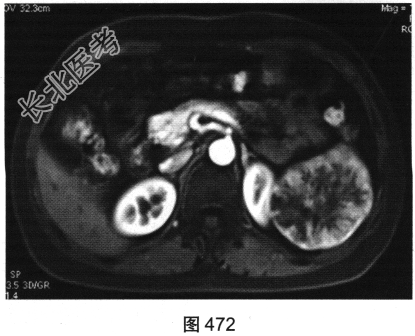

- 多项选择题4.[提示]为进一步明确诊断,患者行MRI检查, 如图470~图473所示。对MRI图像描述正确的是( )

A、T1WI呈不均匀稍低信号

B、左肾被病灶侵犯

C、病灶内见树枝状T1WI低信号、T2WI低信号影

D、门脉期可见造影剂进一步持续充填

E、动脉期轻度强化

F、抑脂T2WI呈不均匀稍高信号

- 多项选择题5.MRI具有很高的软组织分辨率,关于病灶组织成分构成分析正确的是( )

A、囊变

B、出血

C、坏死

D、钙化

E、包膜

F、纤维